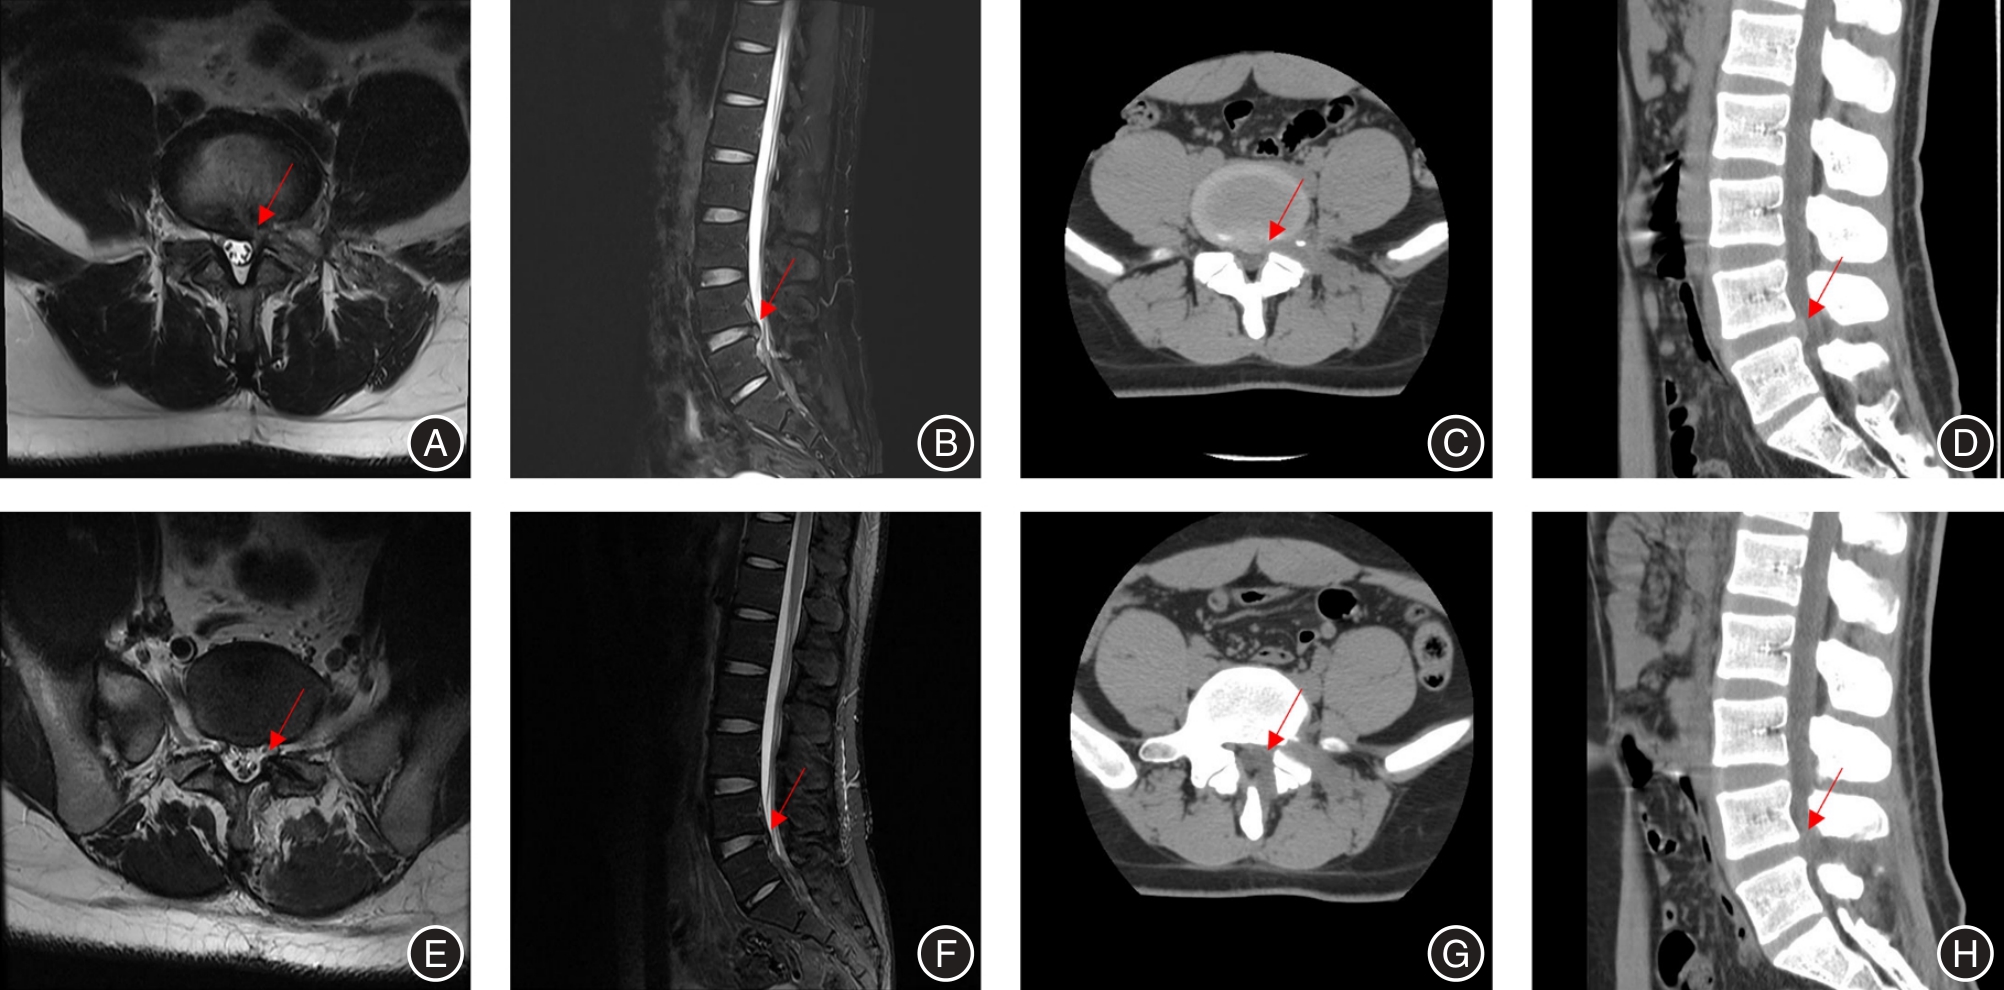

JIANG Q, DING Y, LU Z, et al. Comparative Analysis of Non-Full and Full Endoscopic Spine Technique via Interlaminar Approach for the Treatment of Degenerative Lumbar Spinal Stenosis: A Retrospective, Single Institute, Propensity Score-Matched Study[J]. Global Spine J, 2023,13(6):1509-1521. doi:10.1177/21925682211039181

17 | 蒋强,丁宇,卢正操,等. PE-MFD与Endo-LOVE治疗腰椎间盘突出症疗效比较[J]. 中国骨与关节损伤杂志, 2021, 36 (1): 13-16. |